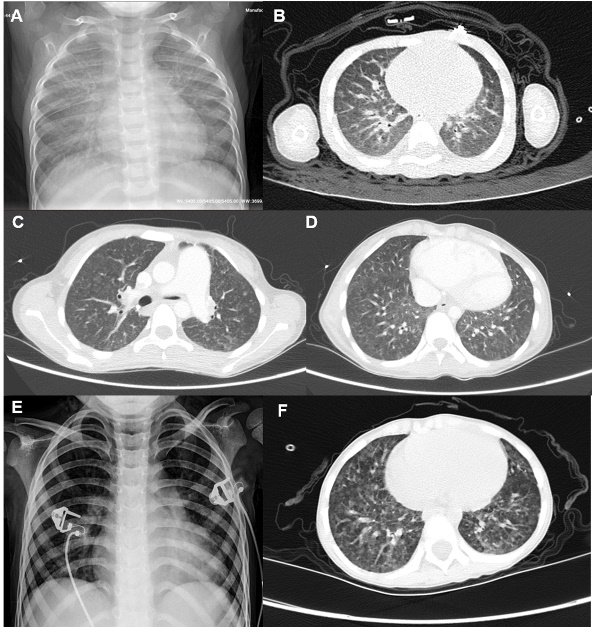

胸部影像学资料见图 1所示,患儿1胸片两肺纹理增多增粗,见片絮影;胸部HRCT见条絮影及网格样改变。患儿2胸部HRCT表现为两肺间质增厚,弥漫小片絮状磨玻璃影。患儿3胸片两肺片絮状密度增高影,胸部HRCT见两肺透亮度欠均匀,弥漫性小斑片状、结节状密度增高影。3例患儿行心脏超声检查,提示不同程度的肺动脉高压,其中2例合并三尖瓣返流,1例合并心包积液。3例患儿均行头颅CT或头颅MRI,未见明显异常。

| A:患儿1胸部X线片示两肺纹理增多增粗、片絮影;B:患儿1胸部HRCT示条絮影及网格样改变;C、D:患儿2胸部HRCT示两肺间质增厚、弥漫小片絮状磨玻璃影;E:患儿3胸部X线片示两肺片絮状密度增高;F:患儿3胸部HRCT示两肺弥漫性小斑片状、结节状密度增高 图 1 MAHCC合并呼吸衰竭患儿胸部影像学表现 |

MAHCC临床表现多样,主要包括:营养不良、生长迟缓,小头畸形,抽搐、意识障碍等神经系统异常,血细胞减少,黄斑病变,肝肾功能不全等,但呼吸系统受累少见[2]。近年来,国内外陆续出现MAHCC合并弥漫性肺病的报道,且报道中合并弥漫性肺病的病例均存在肺动脉高压,但并非所有肺动脉高压的MAHCC患者均存在弥漫性肺病的表现[13-14]。报道中患者胸部HRCT表现为小叶中心磨玻璃结节伴小叶间隔增厚[13],与本研究的患者类似;但既往病例中,未明确提及存在呼吸衰竭情况。本研究中的患儿氧分压均小于60 mmHg,无二氧化碳潴留,呈Ⅰ型呼吸衰竭表现,这可能因本研究中患者存在合并感染而导致氧合障碍的加重。MAHCC引起肺动脉高压的原因可能与同型半胱氨酸对内皮的损伤有关,内皮损伤后肺毛细血管通透性增加,导致血栓的形成和肺小静脉闭塞[15]。目前MAHCC引起肺部病变的原因不明,但亦有可能与肺小血管病变相关,这也与MAHCC的肺部影像学改变吻合[13, 15]。诊断方面,胸部X线无法区分感染和弥漫性肺病,胸部HRCT检查有助于特征性多发边缘模糊的小叶中心磨玻璃样结节改变[13]。对于呼吸衰竭患儿及时完善胸部HRCT是寻找病因的重要步骤。而对于不明原因弥漫性肺病,及时完善血尿代谢筛查、外显子基因检测是明确病因的重要手段。本研究中的患儿通过HRCT检查、尿有机酸测定、血同型半胱氨酸测定、全外显子测序明确诊断。